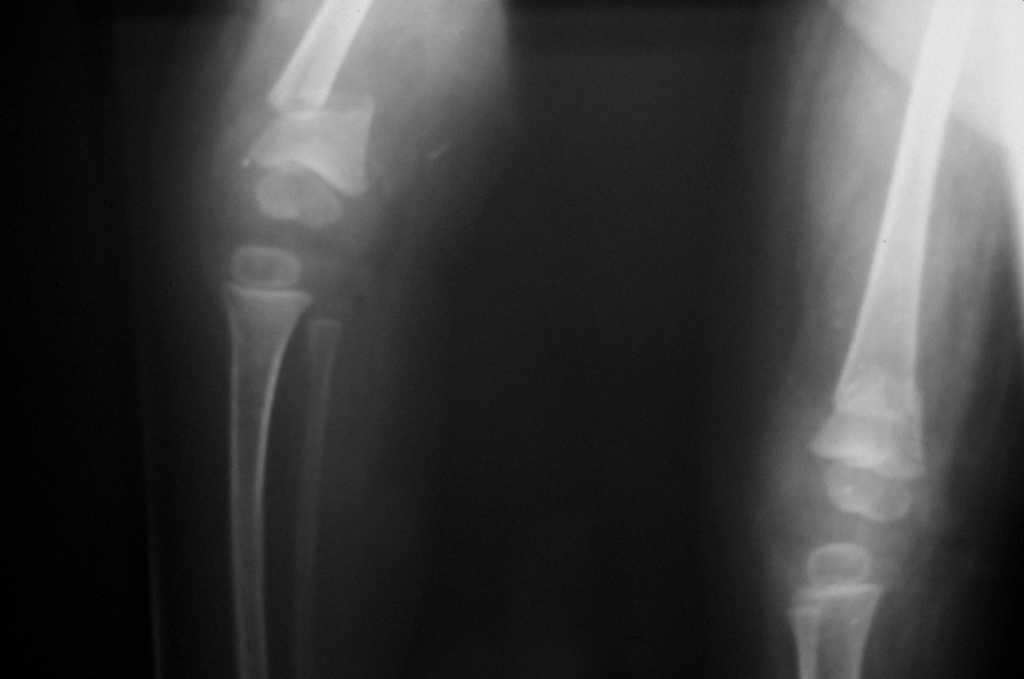

La mayoría de los casos, 10 pacientes, 16 rodillas (63%) fueron diagnosticados y tratados en las primeras 24 horas de vida. Se trata de realizar una tracción manual suave pero intensa, desplazando anteriormente el 1/3 distal fe-moral y a posterior el 1/3 proximal de tibia, corrigiendo la luxación. Se considera la luxación reducida cuando se consigue una flexión de más de 85°-90°, con confirmación radiológica. Es entonces cuando se coloca un yeso manteniendo la posición. Dicha inmovilización es cambiada cada dos semanas. Esta reducción inmediata se logró en 4 de 10 pacientes (6 rodillas) (23% de las rodillas). En los restantes 6 pacientes (10 rodillas) se apreció una resistencia a la flexión con una contractura cuadricipital que impedía la reducción (fig. 2). Entonces se usaron yesos seriados con diferentes grados de flexión en función de la tolerancia de las partes blandas; dichas escayolas eran cambiadas semanalmente, progresando en los grados de flexión. La duración media de la inmovilización con yeso en ambos grupos fue de 90 (42150) días. Del total de las 16 rodillas diagnosticadas y tratadas en las primeras 24 horas, únicamente una (6%) precisó tratamiento quirúrgico. Consistió en una liberación de la cintilla iliotibial.

Figura 2. Control radiológico. Primero de los yesos progresivos.